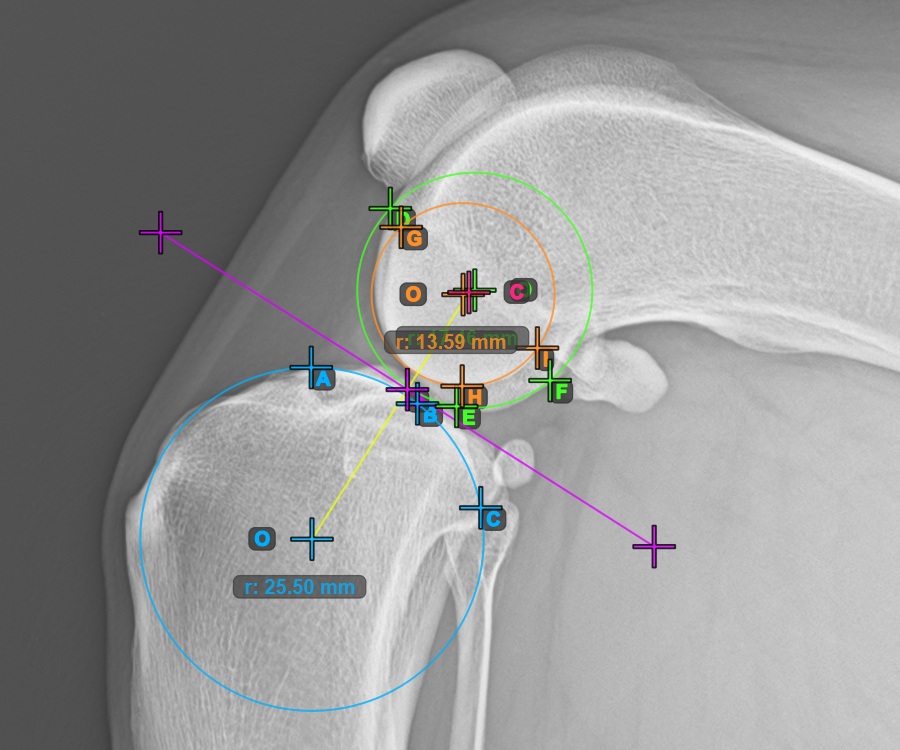

Starten Sie die Messung, indem Sie die drei Punkte am Condylus Medialis Tibialis markieren.

Markieren Sie die drei Punkte am Hauptkondylus des Tibiaknochens (Medialis Tibialis). Unabhängig von der Reihenfolge stellen Sie sicher, dass Sie den vordersten Punkt, den hintersten Punkt und den Mittelpunkt des Medialis Tibialis markieren. Basierend auf den drei gesetzten Punkten wird automatisch ein Kreis konstruiert.

Das Bild unten zeigt die typische Platzierung der drei Punkte am Condylus Medialis Tibialis.